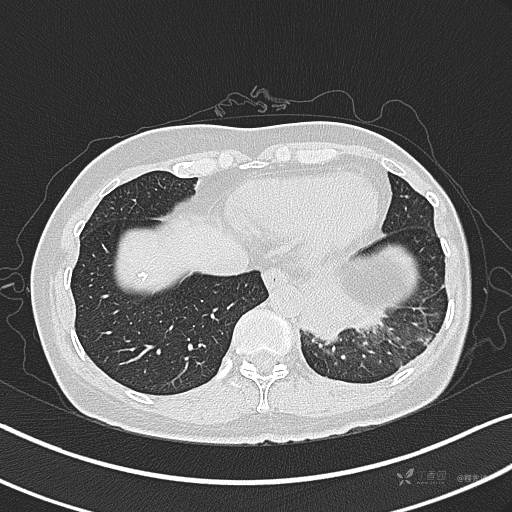

纵隔窗

病灶平扫CT值约31HU

肺窗